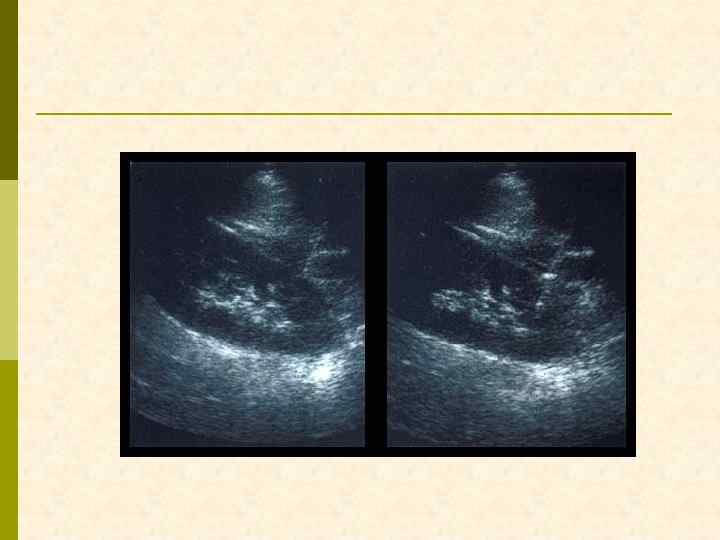

ЛОКАЛИЗАЦИЯ БИОПСИОННОЙ ИГЛЫ ПРИ УЛЬТРАЗВУКОВОМ ИССЛЕДОВАНИИ

ВВЕДЕНИЕ БИОПСИОННОЙ ИГЛЫ В РЕТРОПЕРИТОНЕУМ